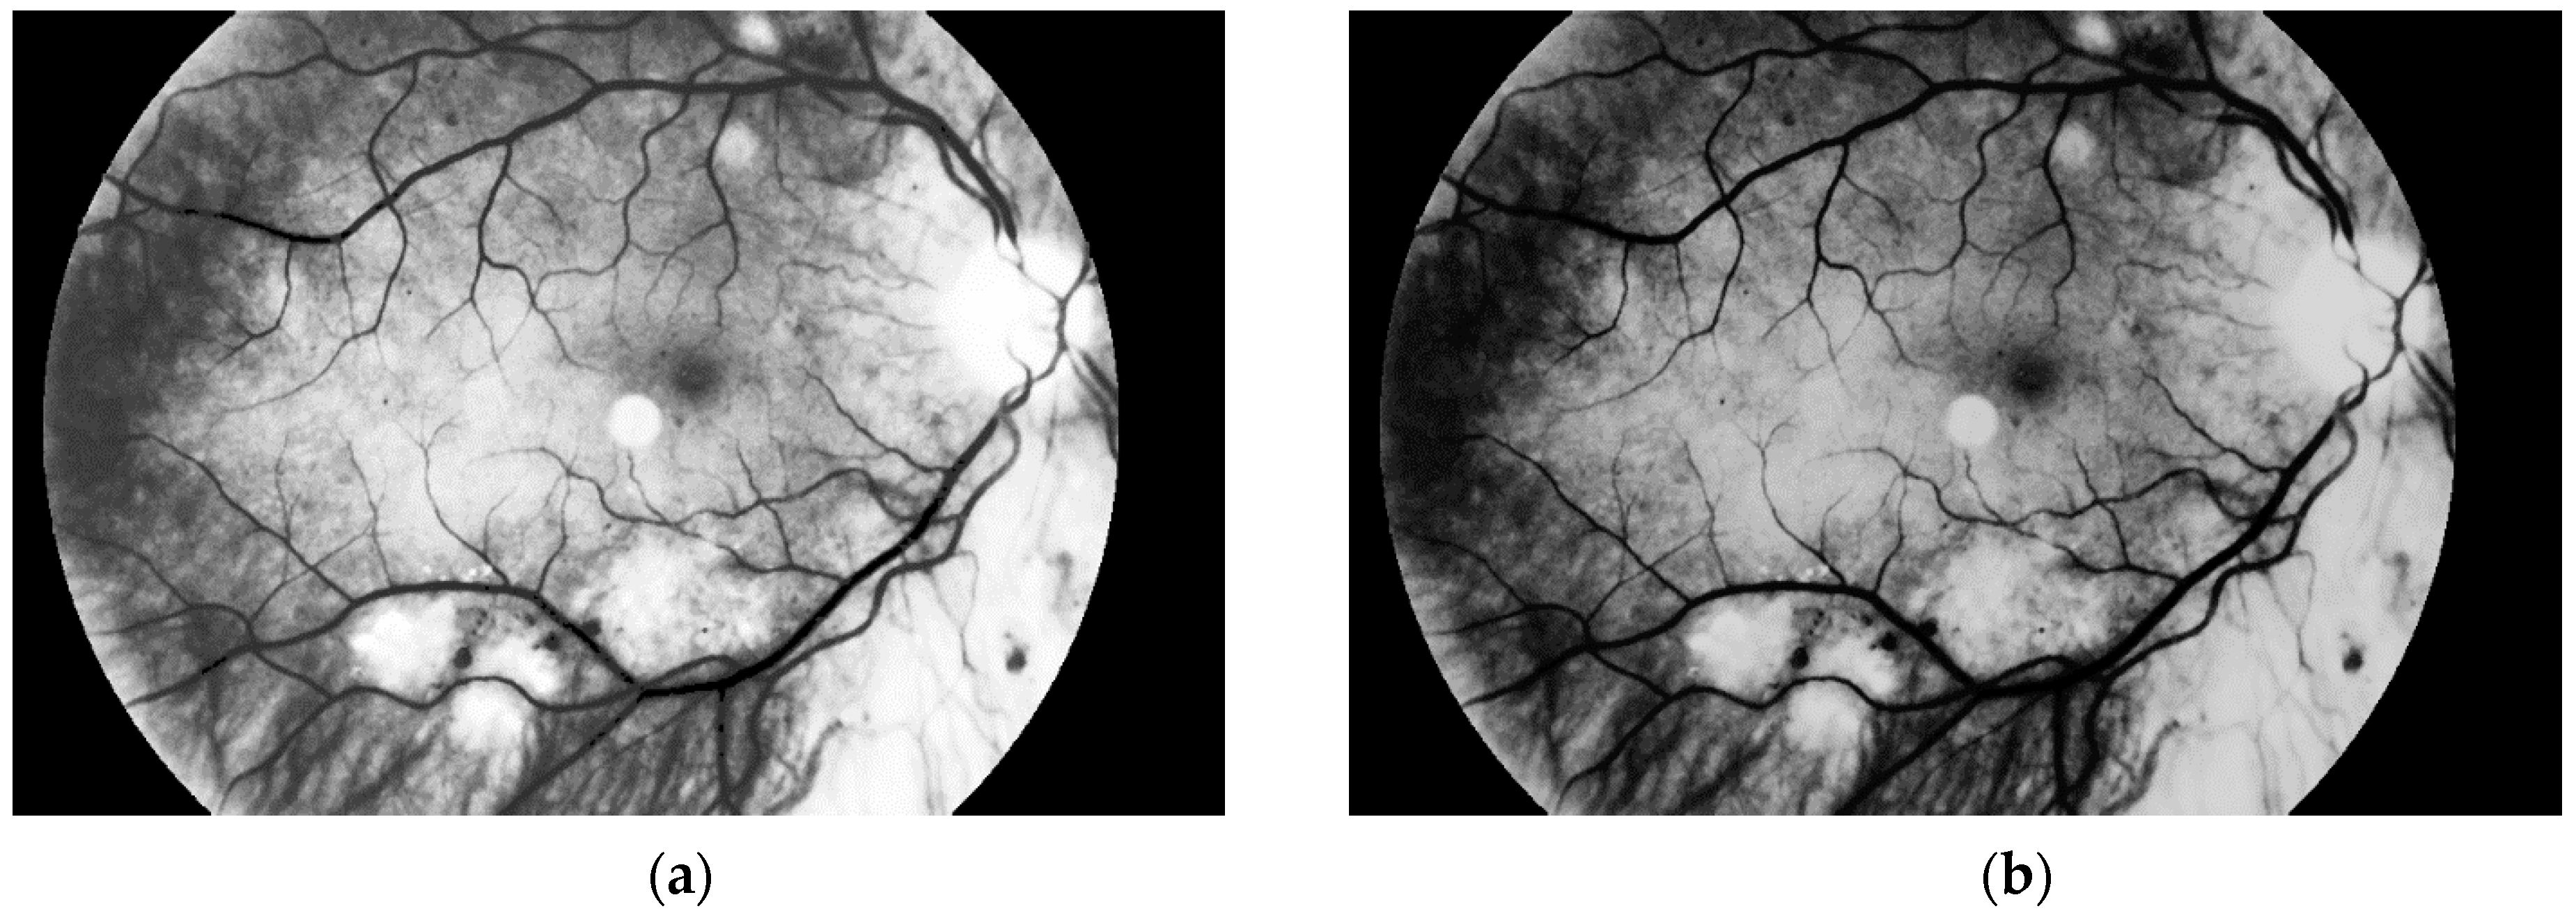

The first step is to load the image. It is then converted to grayscale with green channel. In the literature we have found that this channel is normally used in medical image processing [32,33,34]. The experiments conducted by us have also shown that it gives the best results. It means that the image contains the largest number of the details we are looking for. The visual comparison results between different grayscale conversion methods are shown in Figure 5.

Figure 5. Visual comparison between different grayscale conversion methods: (a) original image; (b) green channel; (c) red channel; (d) blue channel; (e) average value of all channels.

Sensors 19 00695 g005